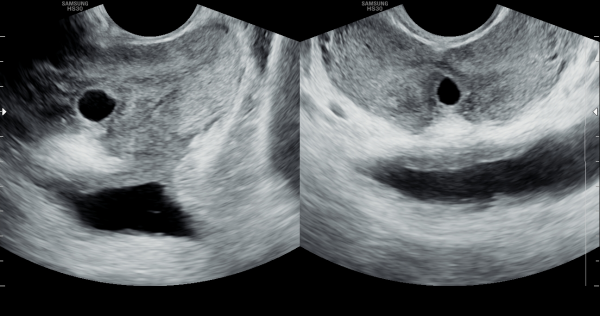

첫 내원 당일 경직장 전립선 초음파 검사상 사정관의 순환 장애로 정낭의 다발성 낭종이 관찰되는 사진입니다.

This is a transrectal prostate ultrasound image taken on the first day of the patient’s visit, showing multiple seminal vesicle cysts caused by impaired circulation in the ejaculatory ducts.

주 2~3회 전립선의 표적 치료후 전립선과 사정관과 정낭 그리고 정관의 순환 장애가 개선되어 정낭의 다발성 낭종이 좋아지고 있는 경직장 정낭의 초음파 사진입니다.

A transrectal ultrasound image of the seminal vesicles showing improvement of multiple seminal vesicle cysts as a result of enhanced circulation in the prostate, ejaculatory ducts, seminal vesicles, and vas deferens following targeted prostate therapy administered 2 to 3 times per week.

주 2~3회 전립선의 표적 치료후 사정관의 순환 장애가 개선되어 사정관의 낭종과 만성 골반통 증후군 그리고 배뇨장애 등의 증상이 개선 되었으나 사정관내 탈락된 상피 세포의 치료와 관리가 필요한

추적 경직장 전립선 초음파 사진입니다.

This is a follow-up transrectal prostate ultrasound image taken after targeted prostate therapy performed 2–3 times per week. The treatment has improved circulation in the ejaculatory ducts, leading to a reduction in ejaculatory duct cysts, chronic pelvic pain syndrome, and urinary symptoms. However, further treatment and management of the exfoliated epithelial cells within the ejaculatory ducts are still necessary.